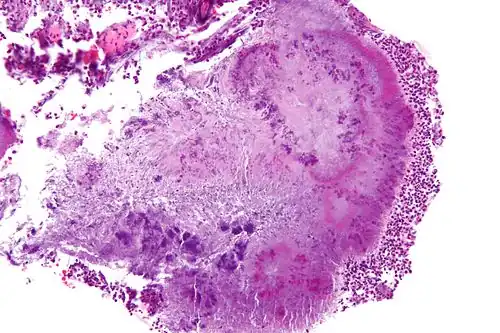

| High-magnification micrograph of a "sulfur" granule formed by Actinomyces in the mandible, H&E stain | |

Actinomyces bovis is a branching, Gram-positive, rod-shaped bacterium of the genus Actinomyces.[1] It is the causative agent of lumpy jaw in cattle, and occasionally causes actinomycosis infections in humans.[3] A. bovis normally populates the gastrointestinal tract of healthy ruminants, but is opportunistic in nature and will move into tissues through ulcerations or abrasions of the mucosa to cause infection.[4] The disease occurs when there is physical damage to the tissue of the mouth, allowing the bacteria to colonize the deep tissue and bone, typically affecting the mandible and maxilla.[5] Actinomycosis is pathognomonic for abscesses containing "sulfur" granules, and its colonies appear basophilic with club-shaped reaction products on a histological preparation.[6][7] Lumpy jaw is commonly treated with broad-spectrum antibiotics with varying success,[8] and can be a major economic loss for producers in countries where it is endemic.[9] Because this organism is zoonotic, it is a human health concern and can cause granulomas, abscesses, skin lesions, and bronchopneumonia.[4]

To diagnose lumpy jaw, the fluids exuding from the bony lump or other abscesses are sampled or aspirated if the infection has not broken through the skin.[18] Tissue samples from the lesion can be examined by histopathology after being embedded in paraffin wax, cut into 4- to 5-mm sections, and stained with hemolysin and eosin stains.[17] The clubs could also be stained by carbol fuchsin with decolourisation by weak hydrochloric acid and counter-staining with methylene blue, Van Gieson's stain, or aniline gentian violet followed by treatment with alcohol.[20] A. bovis can be identified histologically by its basophilic colonies and club-shaped reaction product visible in neutrophilic granulomatous lesions.[17] The club-shapes, also called Spendore-Hoeppli proteins, seen on histological slides are the result of the bacteria being encased in a calcium-phosphate protein complex, as the host attempts to wall off the infection.[17] Another diagnostic feature is the presence of "sulfur" granules,[6] which is pathognomonic for actinomycosis.[17] These granules are small, yellow clumps of exudate that are visible to the naked eye with a similar appearance to grains of sulfur, and are mainly composed of bacterial filaments and host calcium phosphate.[17]